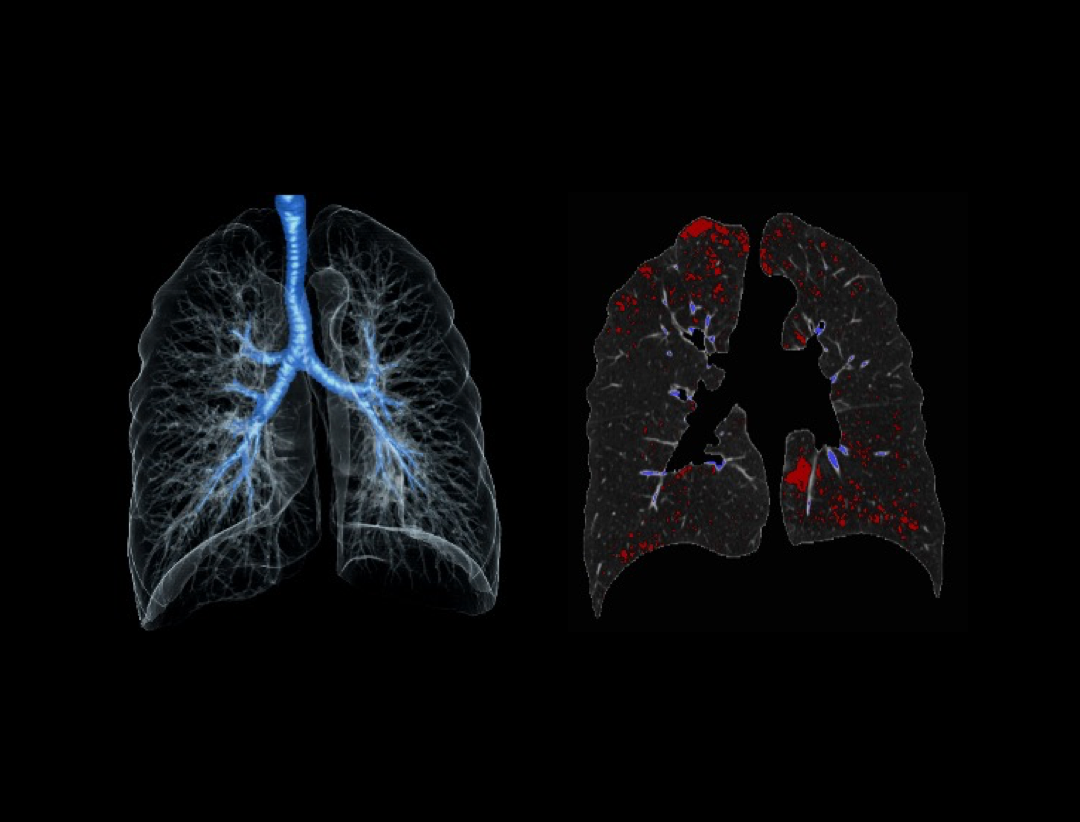

Pulmonary Nodule

Pulmonary Emphysema